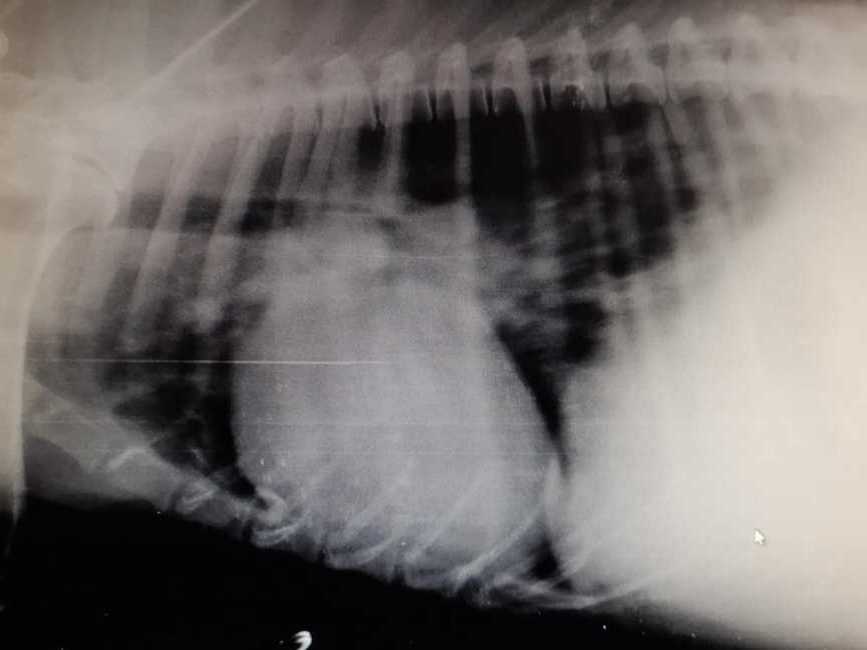

К сожалению, пока предварительный диагноз – Дилатационная кардиомиопатия, Асцит… Нет слов…